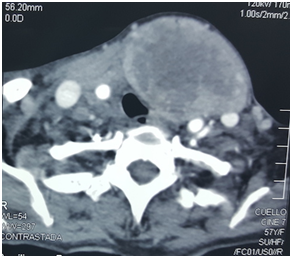

We report the case of a 59-year-old woman who comes to general surgery consultation for a cervical tumor. Woman does not report pathological background. She began one year ago developing an anterior cervical mass with progressive growing, it was painless, without airway obstructions symptoms or difficulty to food ingestion, and for this reason she has not searched medical attention. For the previous 10days she refers weakness, fatigue, and relative incapacity to complete her daily activities. At physical exam she was a female for about 1.60m, 50kg, with an evident anterior cervical tumor of about 12cm of diameter, the tumor was mobile, painless, without airway obstruction or changes in voice tone at parents’ reference, with cardiac frequency of 50 beats per minute, arterial pressure of 100/60mmHg, without other relevant signs. Symptomatology was attributed to thyroid function disturbance and hormonal levels of TSH, T3 and T4 were requested, and a pre-operative evaluation with internal medicine service programmed. One week later this patient come to internal medicine evaluation with increased symptomatology including pallor, bradycardia, tachypnea, and parents refers syncope too. At physical exam she was diaphoretic, with Glasgow of 12 points, pallor, cardiac frequency of 40 beats per minute and arterial pressure of 80/40mmHg, yugular ingurgitation, dyspnea, tachypnea of 27 breaths per minute, diminished peripheral pulses and distal cyanosis. Cardiogenic shock was diagnosed after hormonal levels were confirmed as normal, and patient receive medical treatment with dopamine without significant improvement, requiring advanced airway support 4hours later by Glasgow of 8 points and cardiogenic shock. CT scan reports a compressive, well defined, non-enhancing tumor of 13x7cm, without self-vascularity, dependent of left thyroid hemisphere without occlusion of airway, but compression of left carotid artery (Figure 1). Patient does not improve with medical management and a cardiogenic shock secondary to carotid sinus stimulation was suspected, reason why an emergency thyroidectomy was performed. Left hemi-thyroidectomy was completed with dissection from carotid artery without complications, obtaining a 14x8cm left thyroid lobe (Figure 2) (Figure 3). Patient vital signs improve during the next 12hours allowing extubation and progressive suspension of dopamine infusion. After 24hours’ patient was recovered and asymptomatic from cardiac shock symptoms, confirming our presumptive diagnosis. Histopathology exam reports a multinodular thyroid goiter without malignant cells. After six months follow up patients is asymptomatic.

Figure 1 Cervical CT scan with a 13x7cm well defined non-enhancing tumor, dependent of left thyroid lobe, compressing carotid artery and yugular vein.